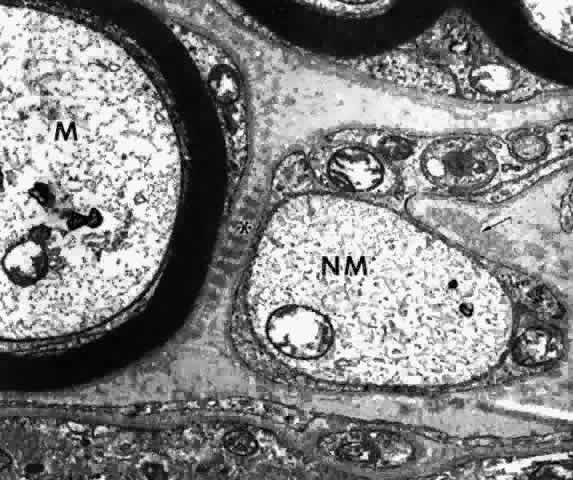

with muscle, nerve, and vascular basement membranes (see Fig. 33), where they appear to serve as anchoring structures. The ultrastructure of the ciliary muscle fibers resembles that of smooth

muscle elsewhere, with a few interesting differences. The muscle bundles

are surrounded by a sheath of flattened fibrocytes rather than primarily

by collagen fibers (Fig. 37),46–48 showing that they belong to the multiunit family of smooth muscles instead

of the syncytial family.49 Each fiber is covered by a continuous basement membrane and has many pinocytotic

vesicles or caveolae on the plasmalemmal membrane. The fiber

is filled with 60- to 70-nm myofibrils that show the usual attachment

densities among them, as well as focally where they attach to the basement

membranes (Fig. 38). These myofibrils are the intermediate filaments of the cell and contain

the protein desmin, used to identify smooth or skeletal muscle cells

by immunohistochemistry. A less specific protein, smooth muscle actin, is

also present but characterizes myofibroblasts as well. Mitochondria

and endoplasmic reticulum are more numerous and Golgi apparatus better

developed than in most smooth muscle cells. Occasional desmosomes

interconnect the cells but no gap junctions. Studies of muscle enzymes

have suggested that there may be functional differences between the

longitudinal muscle and the radial-circular muscle complex.50 The longitudinal muscle cells, particularly their anterior tips, are heavily

fibrillar with fewer mitochondria than the other muscles and have

enzyme characteristics somewhat like those of skeletal rapid twitch

fibers. It is hypothesized that their multiunit structure might allow

the muscle tips to react first in accommodation, stiffening them to counteract

the posterior pull of the remaining muscle on the scleral spur.  Fig. 37. Inset. Thin fingers of fibrocyte cytoplasm (arrows) surround a bundle of

The ciliary muscle is richly innervated with large numbers of cholinergic

nerve terminals. These show primarily the small agranular vesicles

characteristic of cholinergic neuromuscular junctions51 (Fig. 39), consistent with the virtually complete inhibition of ciliary muscle

contraction resulting from use of atropine. Most investigators have described

three types of neuromuscular junctions in the ciliary muscle.46–48,51–53 The most common synaptic junction has an indirect muscle cell contact, with

basement membrane intervening; direct contacts are less frequent (see Fig. 39).  Fig. 39. Dense and lighter muscle fibers (m) around an unmyelinated nerve fiber

Lipofuscin deposition in the muscle cells usually begins after the age

of 50,54 as well as an increase in lysosomal vacuoles, occasional lipid droplets, and

membranous whorls that may derive from degenerate endoplasmic reticulum

or myofibrils no longer anchored to their densities.54,55 THE ANTERIOR INSERTION OF THE CILIARY MUSCLE The possibility that the ciliary muscle fibers insert anteriorly in the